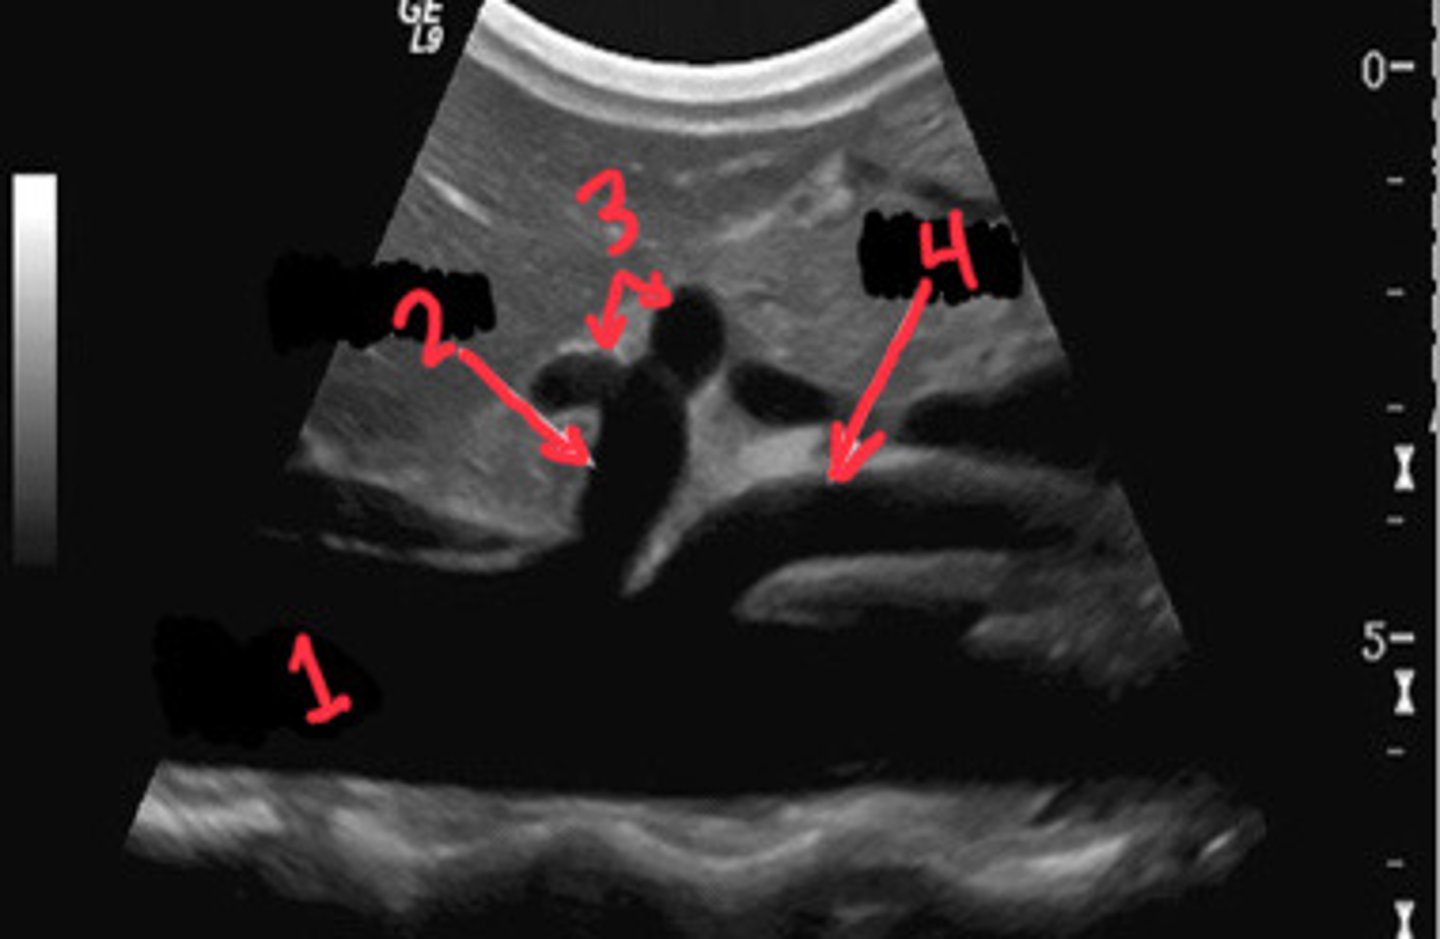

What is 1

CA

What is 2

Branches of the celiac axis

What is 3

SMA

What is 4